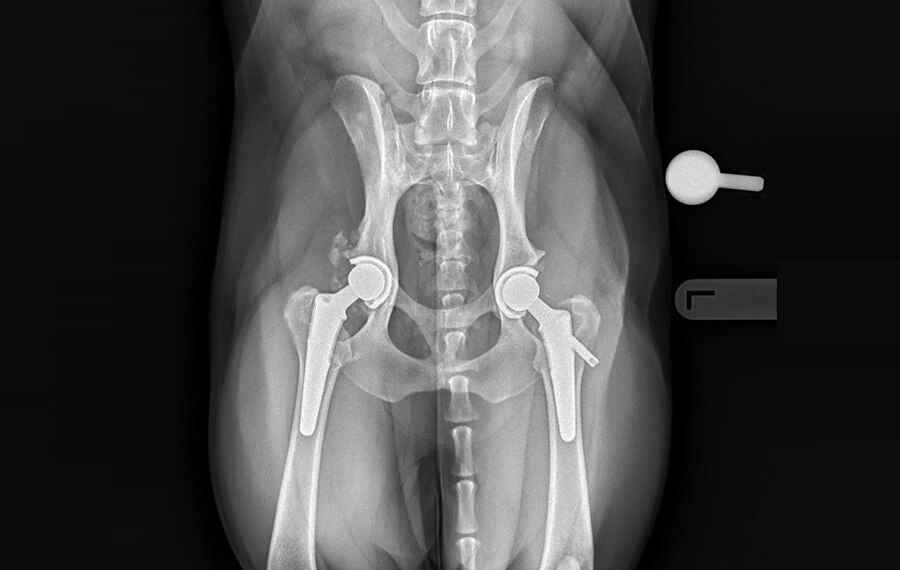

What is Total Hip Replacement?

Total Hip Replacement (THR) involves removing your pet’s diseased hip joint and replacing it with a high-tech prosthetic implant system. By replacing an injured or diseased hip, we can help pets live a normal life without joint pain.

The procedure replaces the two main components of the joint:

The Ball (Femoral Head): The damaged top of the femur is removed and replaced with a medical-grade titanium stem and a polished metal ball.

The Socket (Acetabulum): The worn hip socket in the pelvis is resurfaced with a high-density polyethylene cup.

These components function exactly like a healthy biological joint, eliminating the source of pain entirely. Due to the complexity, hip replacement is an advanced orthopaedic procedure and should only be performed by very experienced orthopaedic surgeons and in clinics set up to perform such procedures safely.